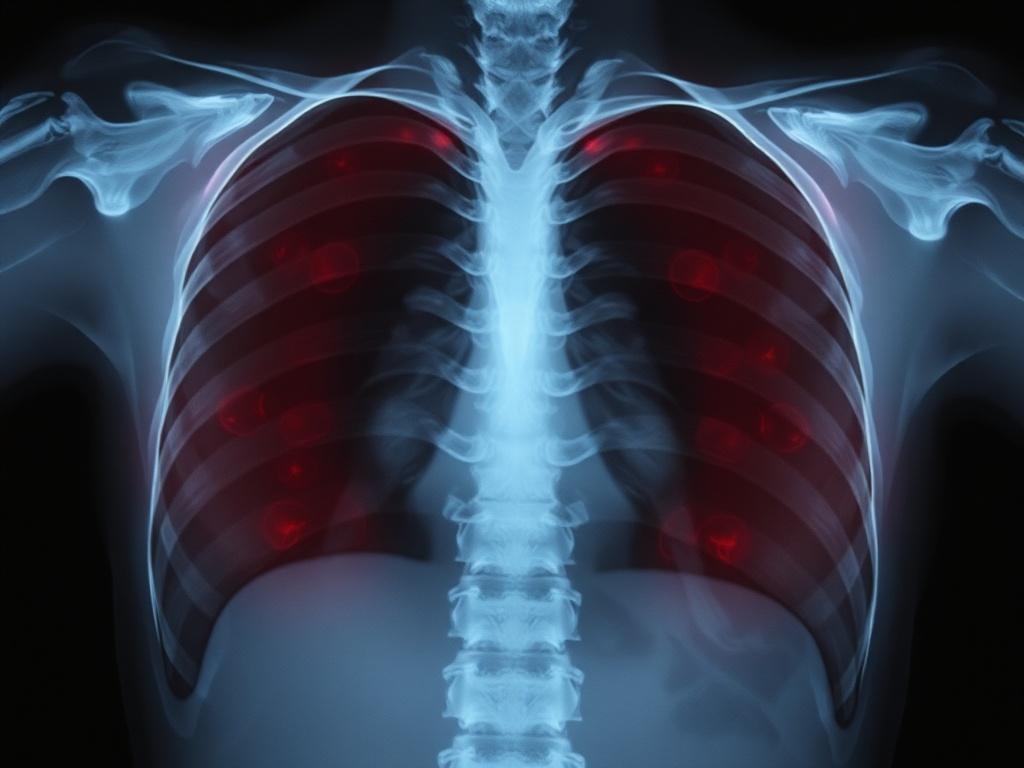

Суть в том, что рентгеновские лучи — это высокоэнергетические фотоны. Они проходят через тело и частично поглощаются тканями в зависимости от плотности и состава. Кости поглощают больше, так что на снимке они выглядят светлыми, а мягкие ткани — темнее. Именно эта разница и позволяет увидеть внутреннюю структуру организма.

Аппарат направляет пучок лучей на область исследования, с другой стороны располагается детектор или пленка. Там формируется изображение, на котором врач распознает патологии. Чем выше контраст между структурами, тем легче поставить диагноз.

Представьте солнечный свет и тень от дерева: чем плотнее объект, тем более отчетлива тень. В рентгене работают те же принципы, только вместо видимого света — рентгеновские фотоны. Кальций в костях дешевле «останавливает» лучи, а воздух в легких почти не мешает, поэтому легкие выглядят темными.

| Рентген грудной клетки | Легкие, сердце, плевра | Кашель, подозрение на пневмонию, контроль состояния |